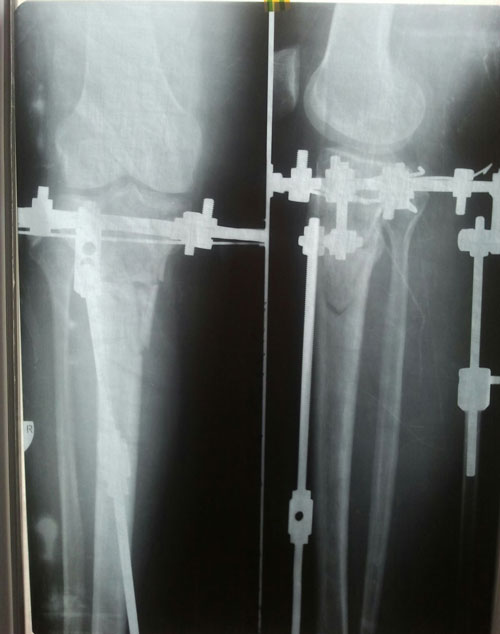

В процессе исправления деформации ног.